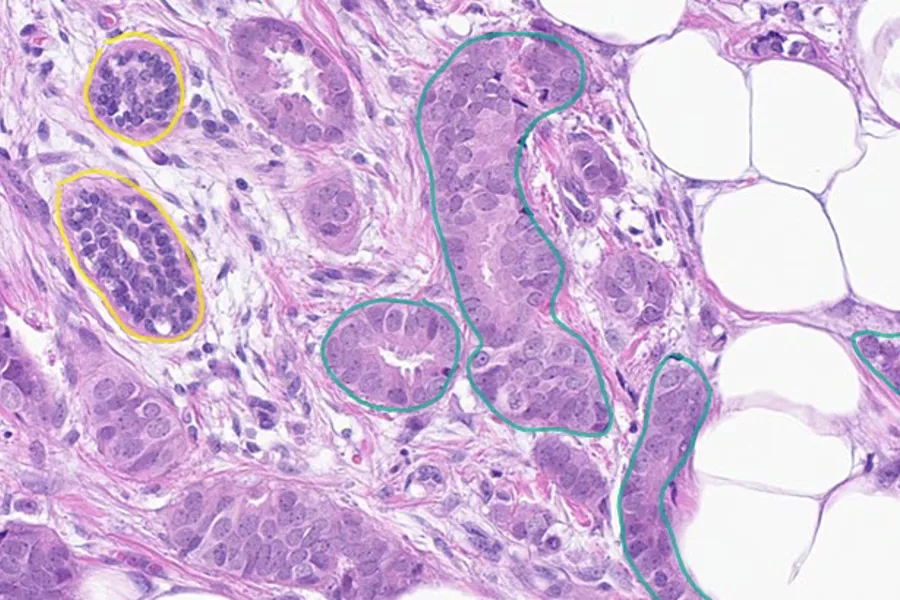

Breast cancer affects more than 2 million individuals globally each year. An important part of the diagnostic process is to assess proliferation in the tumour tissue, which is an indicator of how quickly the cancer is growing. It can give insight into the likely outcome of a patient and whether or not the patient should receive chemotherapy. This prognostic evaluation is currently performed by a visual assessment which involves counting cancer cells (see examples in the figure below).

Figure: In the top left image, mitotic cancer cells are marked and counted in HE stained breast tumour tissue. In the top right, breast tumour tissue is stained to detect the proliferation marker Ki67. Cells that are positive for this marker appear brown, whilst negative cells appear blue. The higher the % of brown (positive) cells, the poorer the prognosis. In the bottom panel is an example of how AI methods can be used to identify highly proliferative regions and these can then be counted automatically.